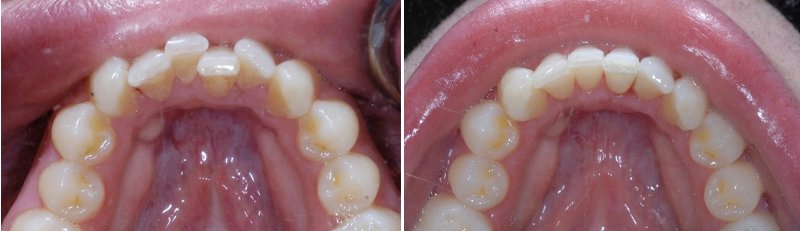

儿童牙齿矫正前后对比

小孩牙齿的畸形程度影响牙齿矫正的价格,我们都知道牙齿畸形的程度较轻时,其治疗的难度就会比较小,因此在进行牙齿矫正时的价格也会相对较低一些。相反的话牙齿畸形程度比较严重时,治疗的难度也会相对加大,因此在进行牙齿矫正时的价格也会相对的提高一些。